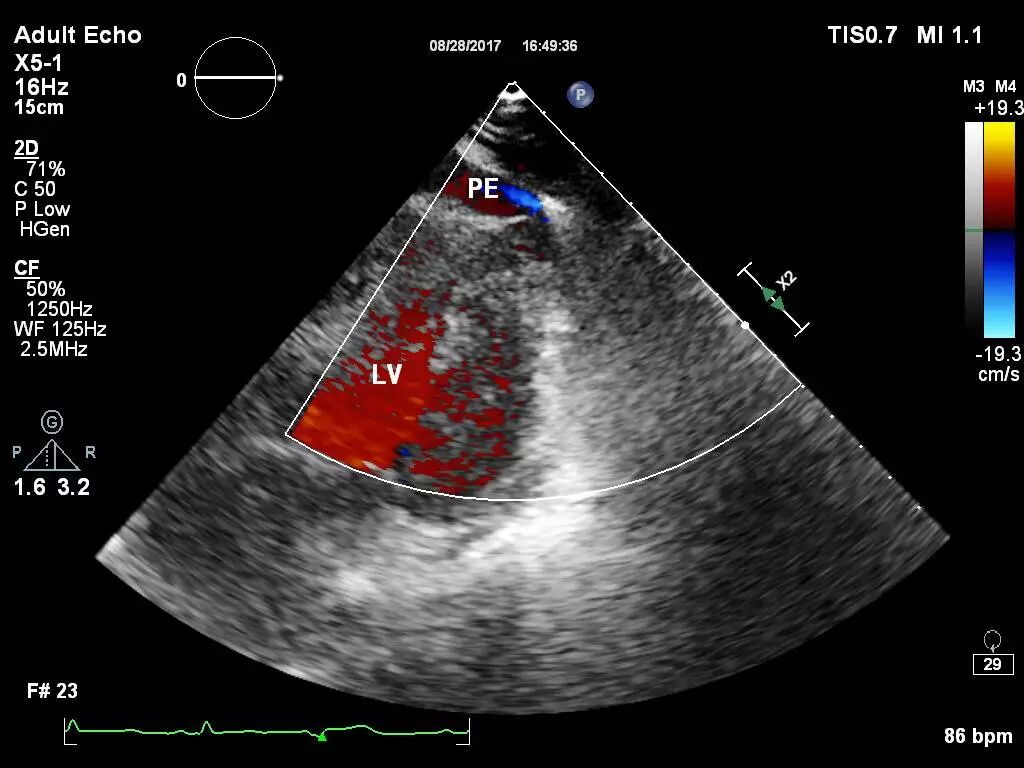

图1和图2 :术中行心包积液彩超可见:心包腔内见液性暗区:右房顶部  20mm,右室前壁最多时25 mm,右室侧壁旁15 mm。提示:心包积液(中大量)。

图3和图4: 彩色多普勒:心包腔可见可疑的较明亮彩色信号。